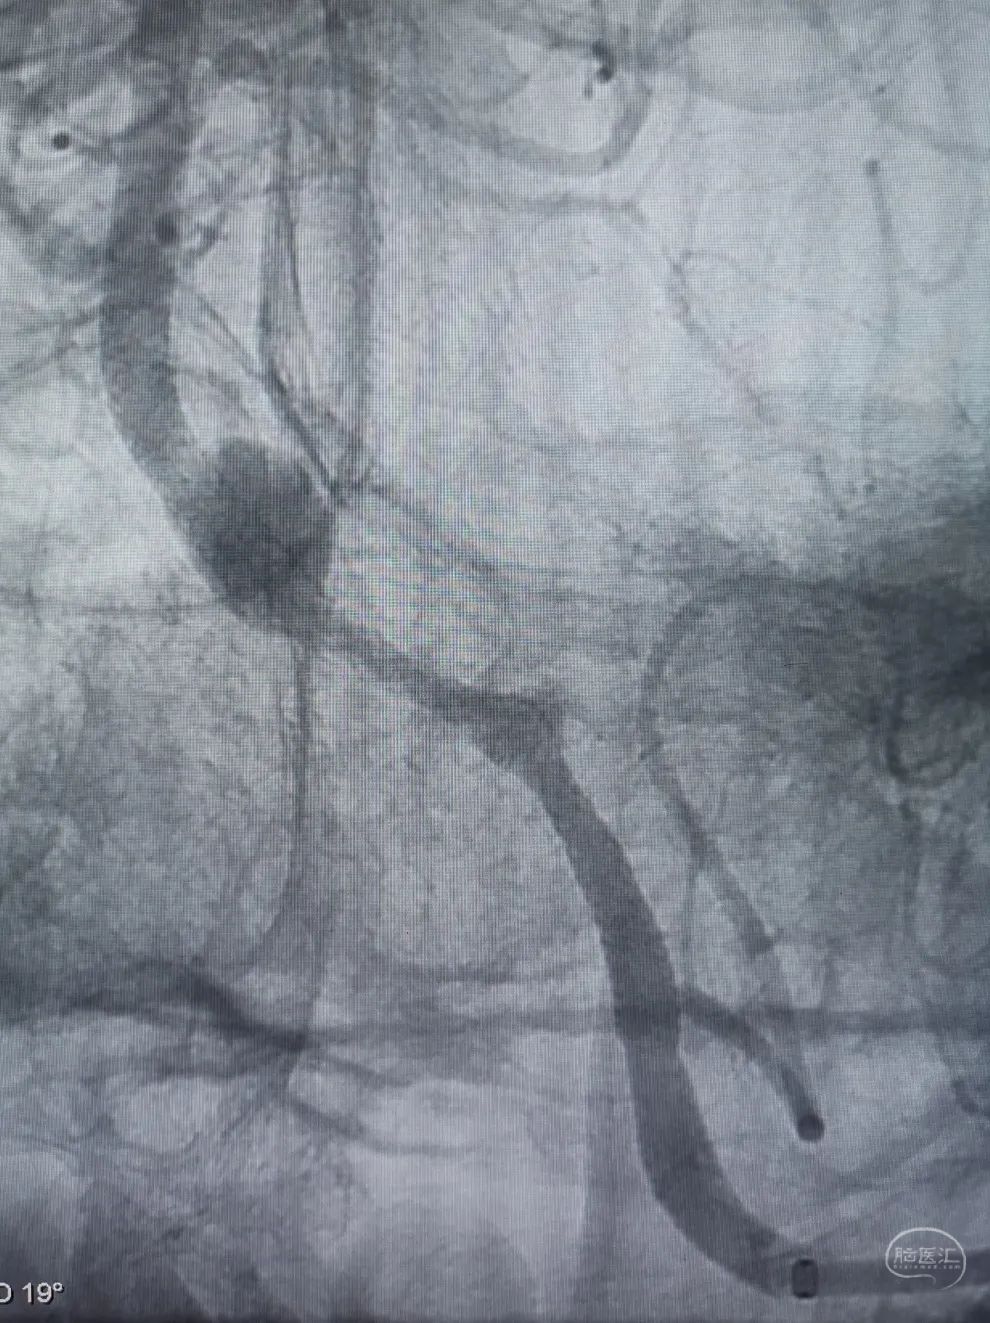

股动脉入路,置入8F长鞘,6F 115cm Navien™ 颅内支撑导管超选至左侧椎动脉V4段。

将Phenom™ 27微导管超选进入左侧大脑后动脉内,释放一枚3.25×35mm Pipeline™ Flex血流导向密网支架,远端定位在动脉瘤以远7mm,在动脉瘤处推密,近端定位在PICA起始部上端或远端,支架打开顺利。导引导管内推注替罗非班12mL,支架导管及微导管常规按摩,促进支架贴壁。

术后造影显示动脉瘤内造影剂滞留明显,载瘤动脉通畅。